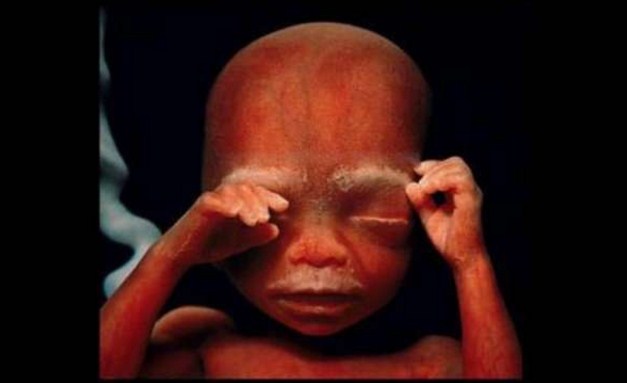

На 10 седмици ембрионът вече използва ръцете си, за да изучава околната среда.

16 седмици.

Кръвоносните съдове се виждат през кожата.

18 седмици. Зародишът вече може да чува звуци от външния свят.